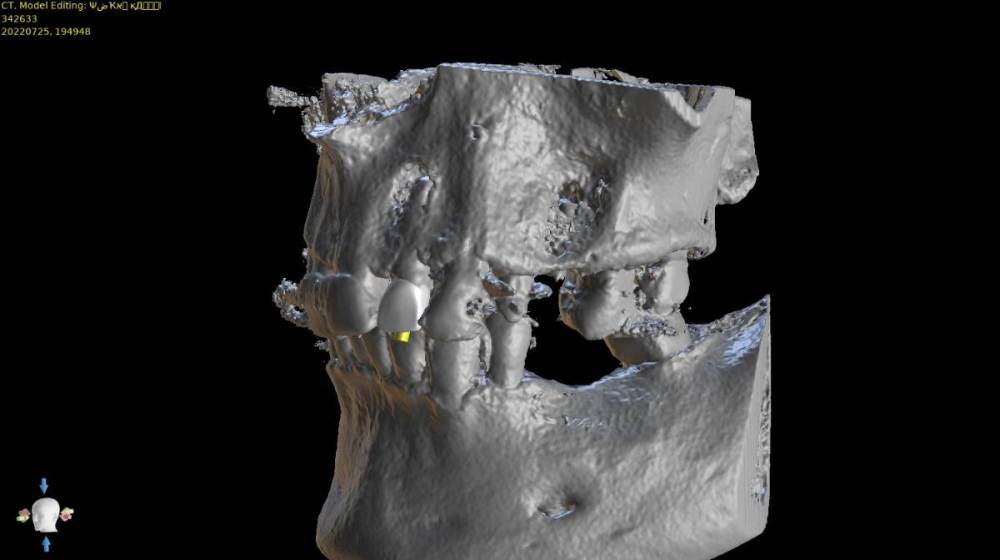

TIGER Опубликовано 10 августа, 2022 Поделиться Опубликовано 10 августа, 2022 @Женька ставил бы сразу с IDR -B2S? Ссылка на комментарий

Женька Опубликовано 12 августа, 2022 Автор Поделиться Опубликовано 12 августа, 2022 (изменено) @TIGER меня размеры дефектов смущают очень сильно. понимаю, что идр лучше, но вариация со смарт билдером по идее тоже должна сработать? Изменено 12 августа, 2022 пользователем Женька Ссылка на комментарий

Raystom Опубликовано 12 августа, 2022 Поделиться Опубликовано 12 августа, 2022 @Женька со смартбилдером при таких дефектах получите огромные проблемы 1 Ссылка на комментарий

TIGER Опубликовано 12 августа, 2022 Поделиться Опубликовано 12 августа, 2022 @Raystom плюсую Ссылка на комментарий